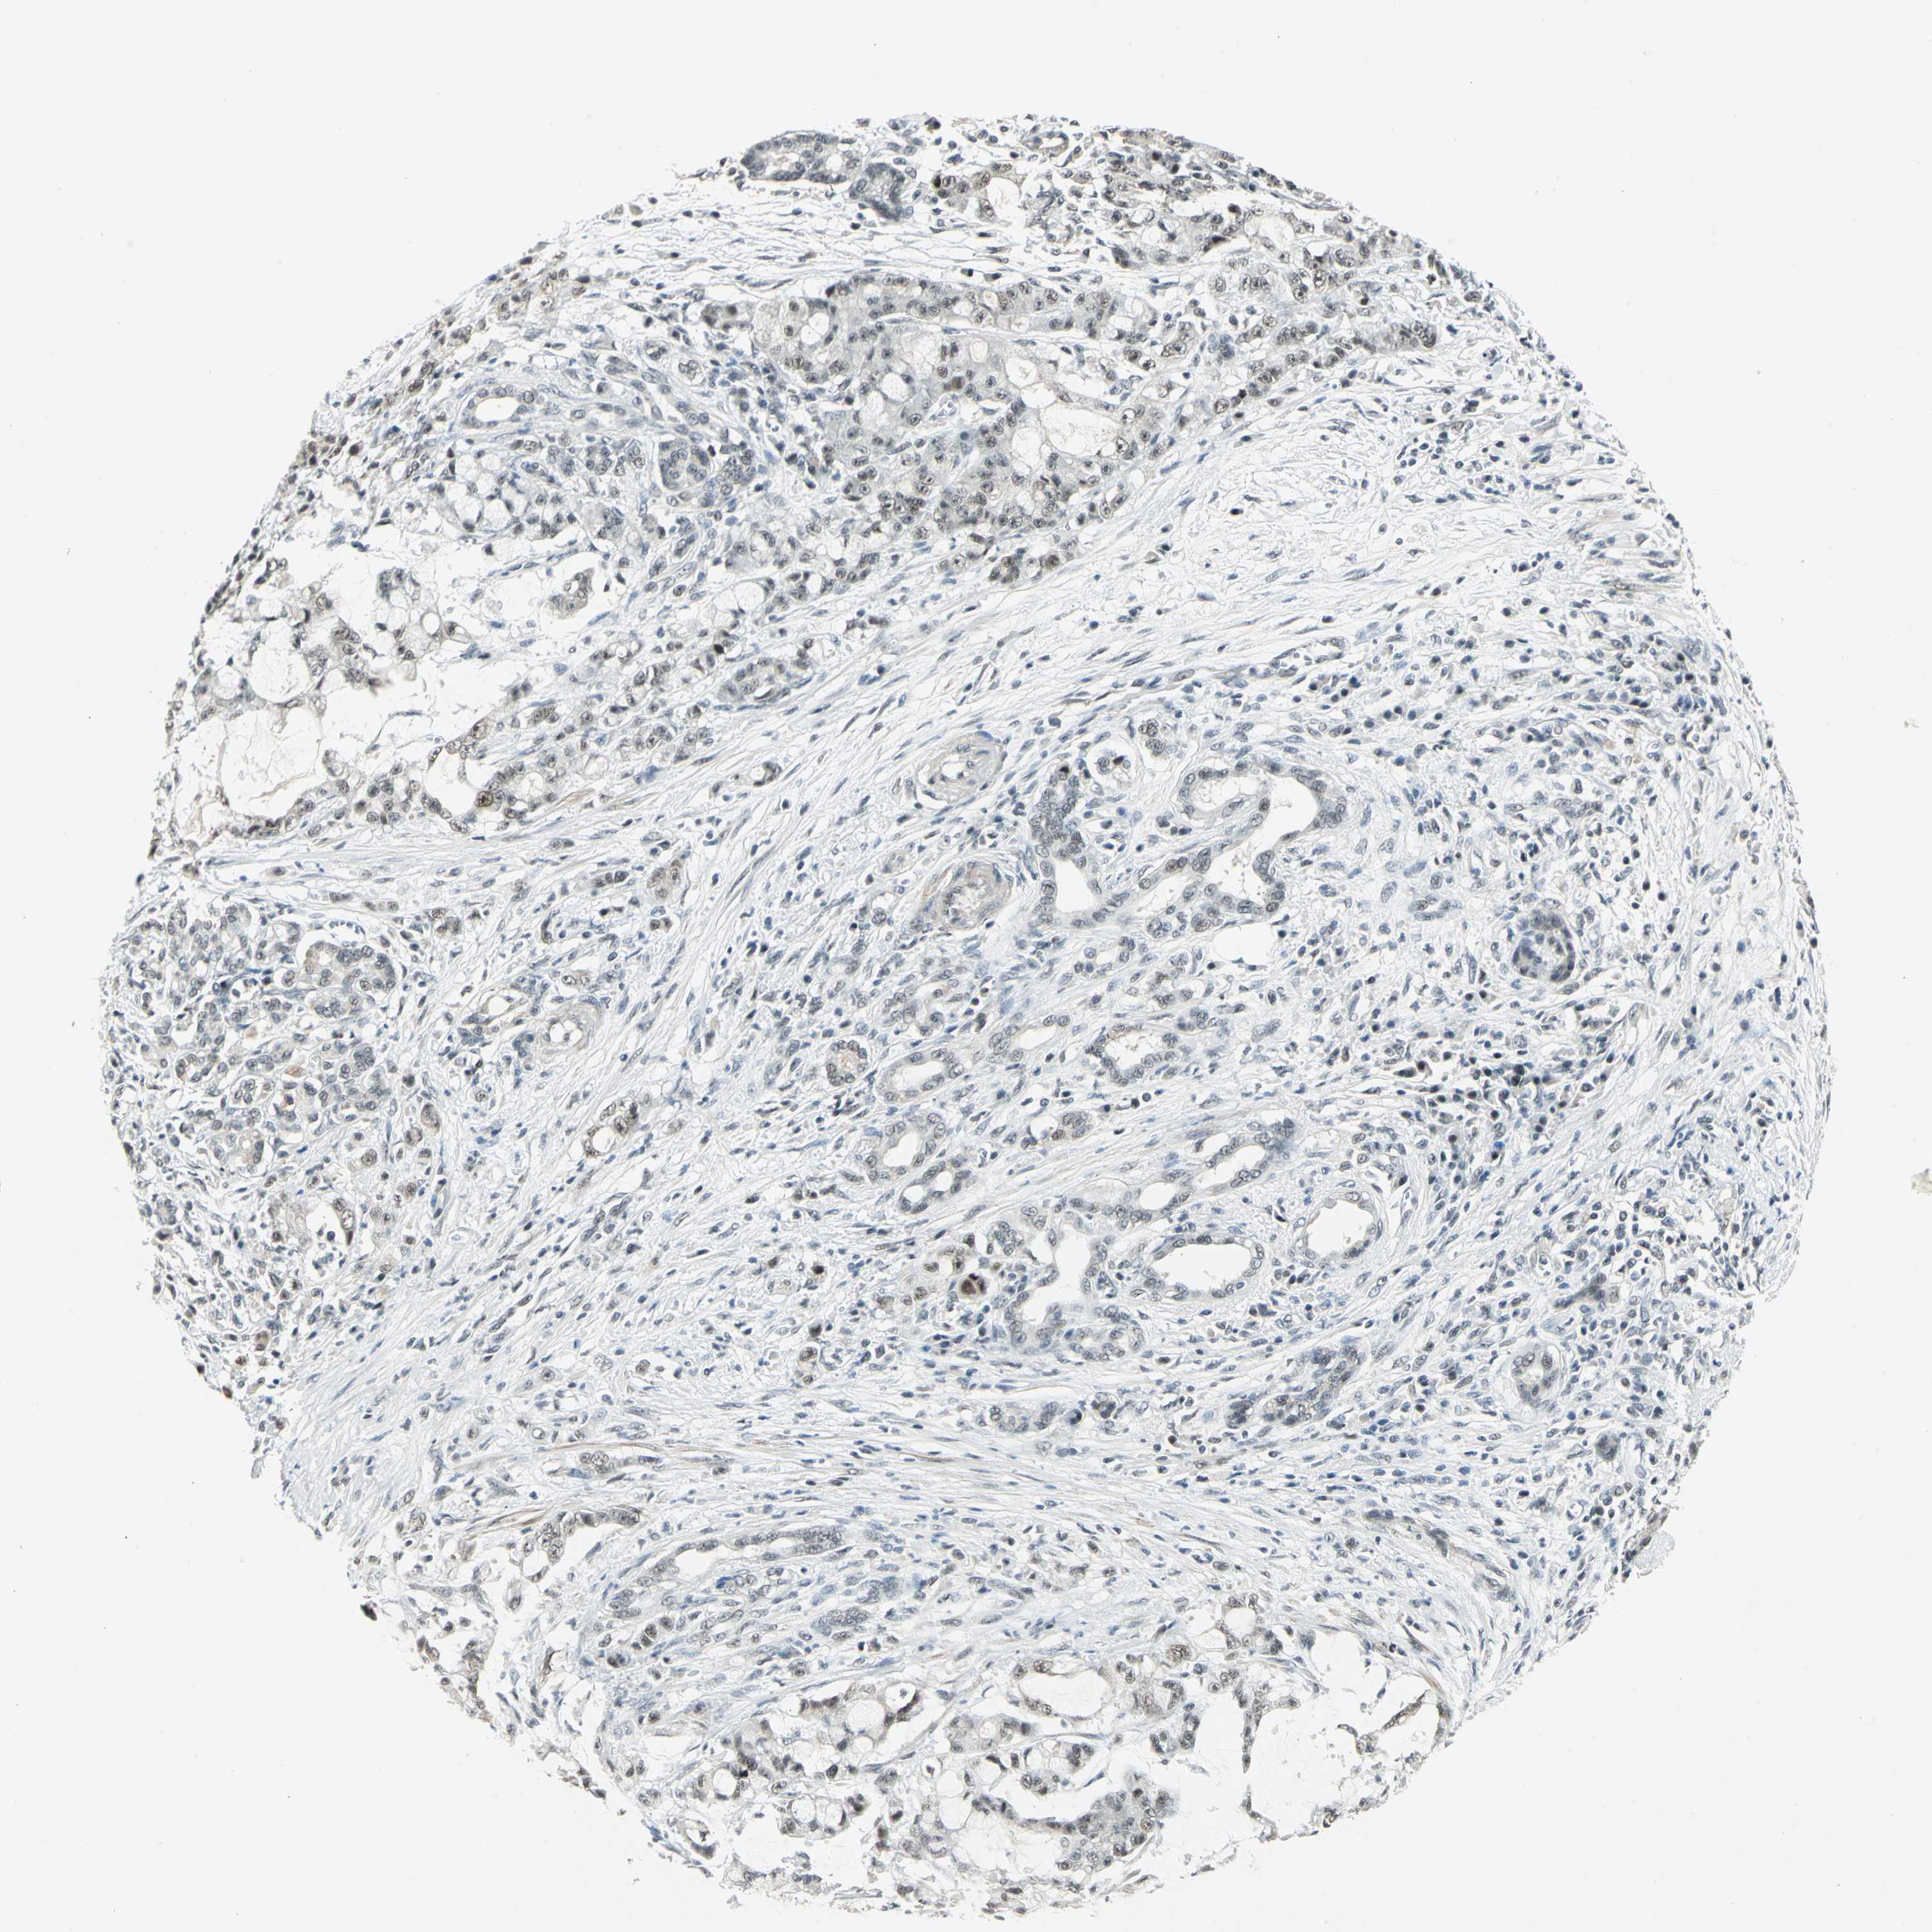

PANCREATIC CANCER - Protein expressioni

A mouse-over function shows sample information and annotation data. Click on an image to view it in a full screen mode. Samples can be filtered based on level of antibody staining by selecting one or several of the following categories: high, medium, low and not detected. The assay and annotation is described here.

Note that samples used for immunohistochemistry by the Human Protein Atlas do not correspond to samples in the TCGA dataset.

Antibody stainingi

Antibody staining in the annotated cell types in the current human tissue is reported as not detected, low, medium, or high, based on conventional immunohistochemistry profiling in selected tissues. This score is based on the combination of the staining intensity and fraction of stained cells.

Each image is clickable and will lead to virtual microscopy that enables deeper exploration of all samples and also displays staining intensity scores, fraction scores and subcellular localization as well as patient and tissue information for each sample.

Antibody HPA005544

Antibody CAB004508

Staining

High

Medium

Low

Not detected

Intensity

Strong

Moderate

Weak

Negative

Quantity

>75%

75%-25%

<25%

None

Location

Nuclear

Cytoplasmic/membranous

Cytoplasmic/membranous,nuclear

Adenocarcinoma, NOS